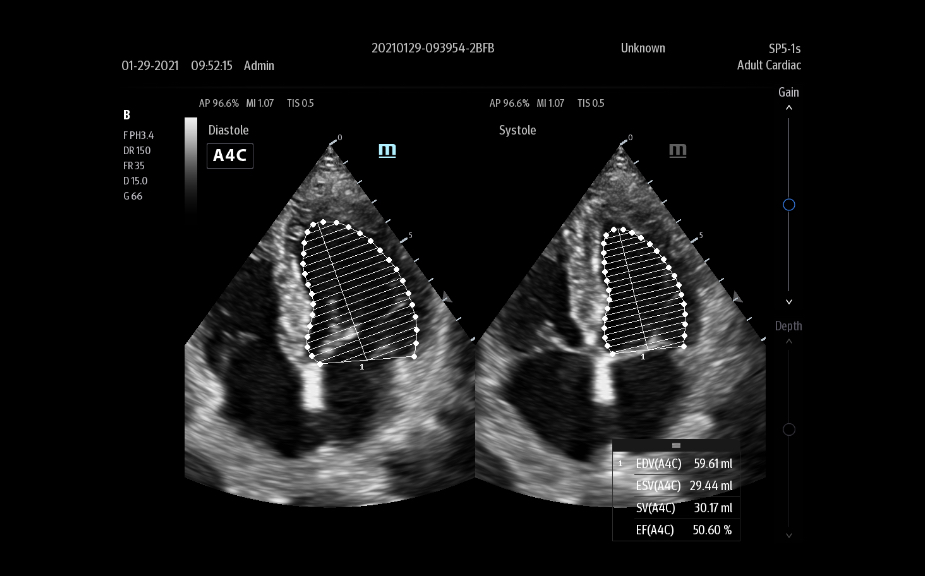

El sistema de ultrasonido TE9 estĂĄ dise?ado para ayudar a facilitar una mejor atenciĂłn al paciente y ampliar las capacidades de imagen para aplicaciones de anestesia, emergencias y cuidados crĂticos. Con funciones avanzadas, una gran pantalla tĂĄctil y una tecnologĂa de imagen superior, el TE9 es ideal para ayudar a mejorar la eficiencia clĂnica y la confianza en el diagnĂłstico. Las herramientas de automatizaciĂłn inteligentes brindan mediciones rĂĄpidas y reproducibles para exĂĄmenes y procedimientos fiables, incluso en entornos de gran presiĂłn.